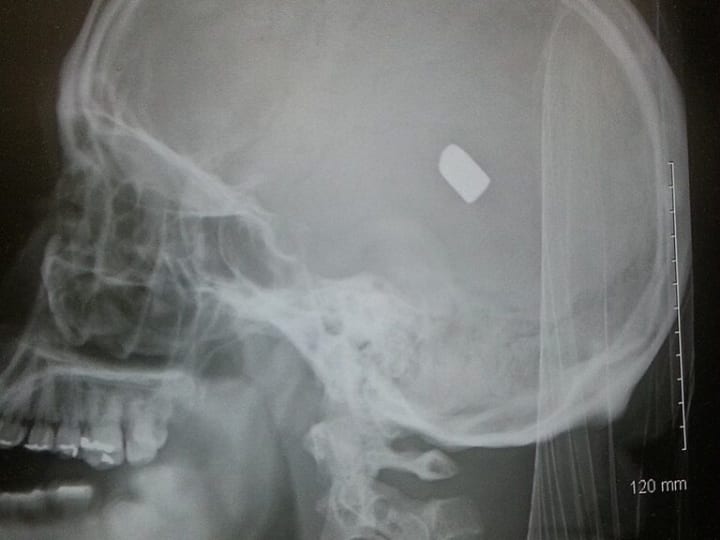

Frustrating headaches and memory loss sent Nicole to a doctor for help. She learned a bullet was lodged in her head -fired by her boyfriend after an argument.

In the spring of 2017, Nicole Gordan suddenly began having headaches -terrible headaches accompanied by slurred speech and memory loss. Gordon went to the doctor about a month into the symptoms, hopeful she’d find out the cause and get treatment going. That’s when she learned shocking news: she’d been shot and bullet fragments were lodged in her head. Gordon had no recollection of a gun ever being pointed in her direction, much less ever getting shot.

Police never located the firearm or bullet casings and doctors did not remove the bullet from her skull.

Any effort “to remove the projectile could cause the victim’s death,” a Fulton County District Attorney press release stated.